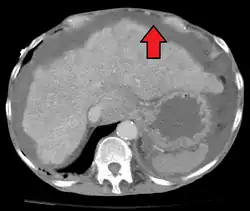

Diagnostic method | Physical exam, ultrasound, CT scan[3] |

Ultrasound investigation is often done before attempts to remove fluid from the abdomen. This may reveal the size and shape of the abdominal organs, and Doppler studies may show the direction of flow in the portal vein, as well as detecting Budd–Chiari syndrome (thrombosis of the hepatic vein) and portal vein thrombosis. The sonographer also can estimate the amount of ascitic fluid, and difficult-to-drain ascites may be drained under ultrasound guidance. An abdominal CT scan is more accurate than a sonogram to reveal abdominal organ structure and morphology.[13]